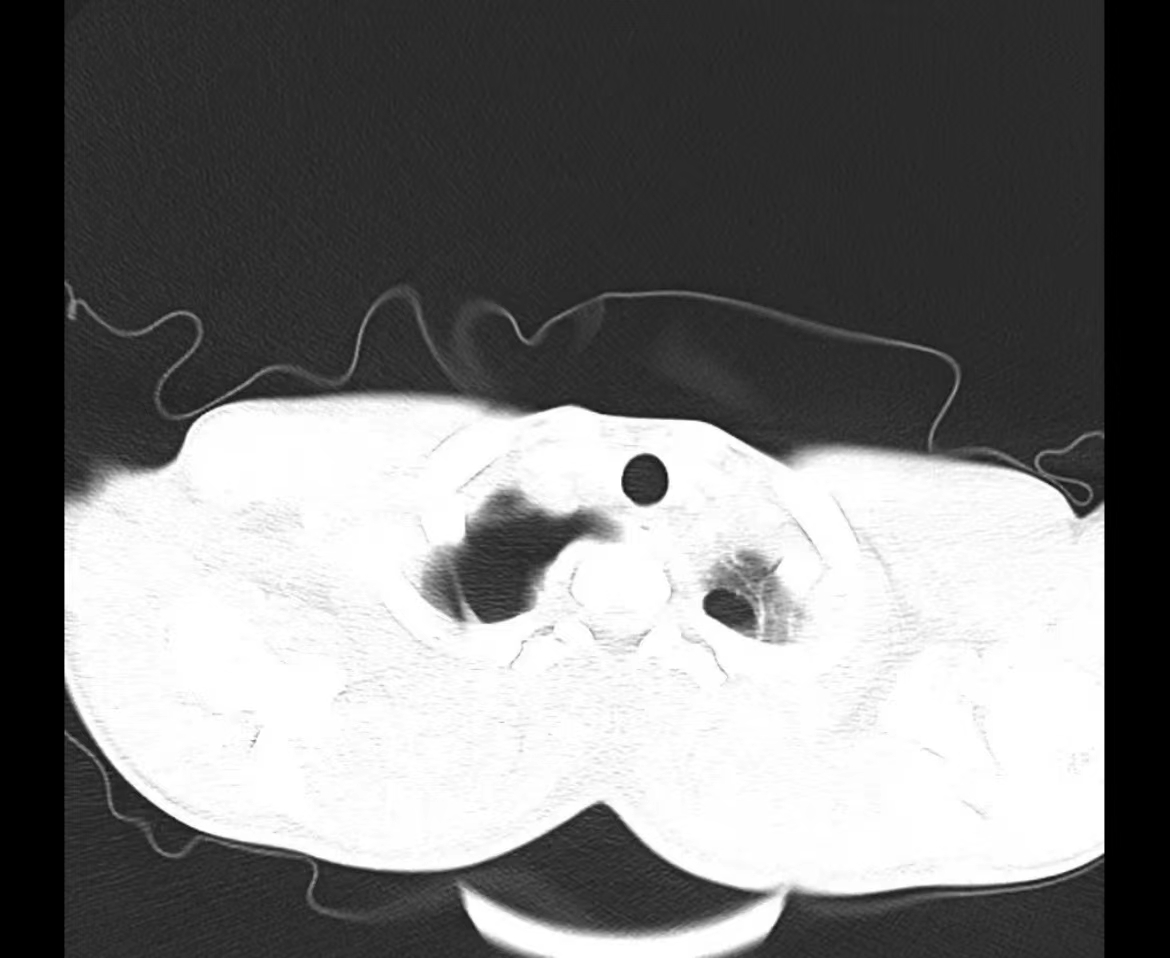

夜班急诊来了一位老大娘,捂着胸口来到CT室说:“医生,快帮我检查一下吧,看我出了什么毛病,胸口痛得厉害,出气都可疼,还闷得慌!”。于是立马登记完检查信息、赶紧给她进行CT扫描,结果一看是气胸,图像如下:

老大娘下了扫描床便说:“都怪我家那儿子,30好几了还不结婚,还没说他两句还给我顶嘴,给我气得直哆嗦,然后我就开始这样了”。看来肺还真能被“气炸”了啊!